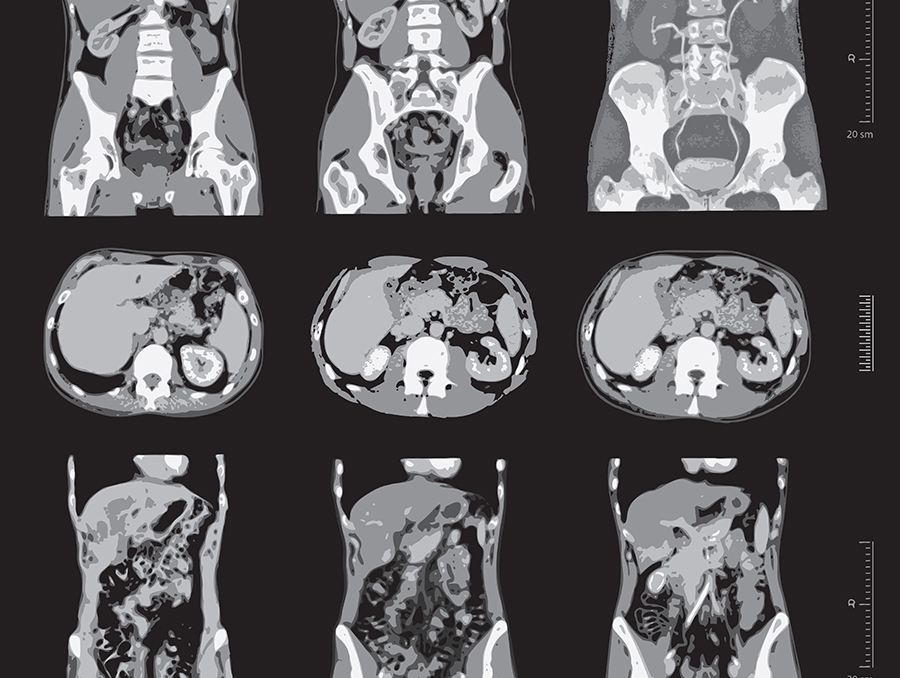

CT კვლევა კონტრასტით

რამდენად ინფორმაციულია კონტრასტული კვლევა?

კონტრასტული კვლევა, როგორც წესი, ბევრად უფრო ინფორმაციულია, ვიდრე უკონტრასტო. კონტრასტი იძლევა საშუალებას:

უკეთ დავინახოთ სიმსივნური პროცესები. კონტრასტი გროვდება სიმსივნურ უჯრედებში და ეხმარება მათ მკვეთრად დიფერენცირებას ჯანსაღი ქსოვილებისგან.

შეფასდეს სისხლძარღვების მდგომარეობა. კონტრასტი აჩვენებს სისხლძარღვების შევიწროებას, ანევრიზმებსა და სხვა პათოლოგიებს.

დადგინდეს ანთებითი პროცესები. ანთებითი უბნები ხშირად იზიდავს კონტრასტს, რაც ეხმარება დაავადების ზუსტად ლოკალიზებას.

ამიტომ, ექიმის რეკომენდაცია, რომ ჩატარდეს კონტრასტული კვლევა, მიმართულია ზუსტი დიაგნოზის დასასმელად.